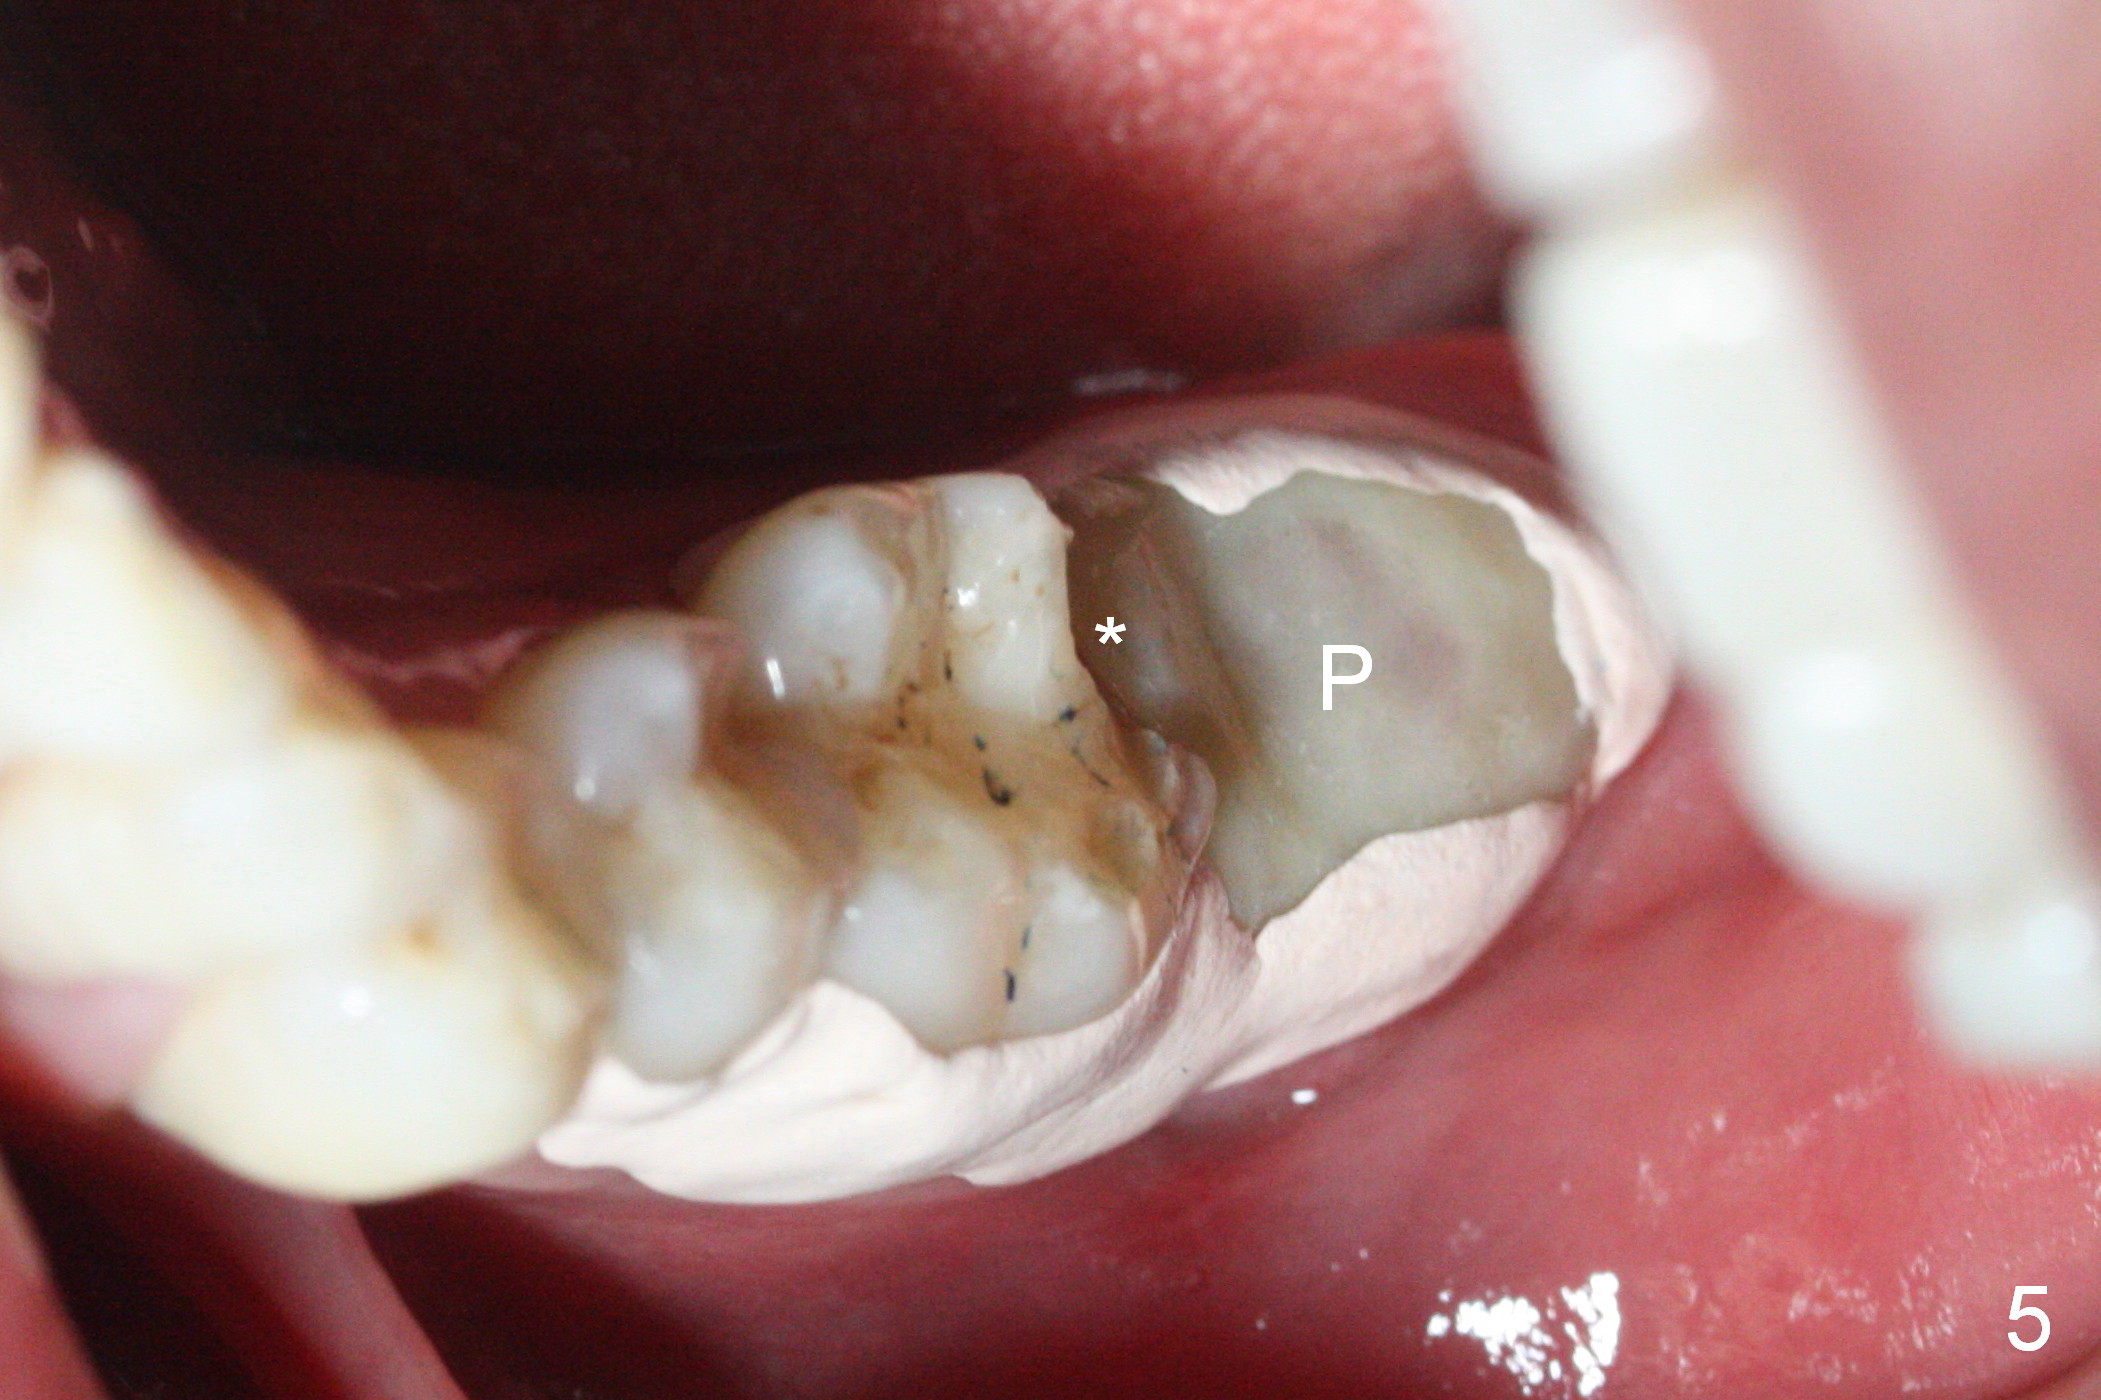

When the tooth #18 is extracted, the buccal and lingual plate are absent. Initial osteotomy is established in the middle of the socket (Fig.1). After 4.3 mm Magic Drill (15 mm from the buccal gingival margin, new bone ~ 4 mm), a 5x9 mm IBS dummy implant is placed with correct trajectory (Fig.2). Since the bone density is seemingly high, the same size of a definitive implant is placed with primary stability. The trajectory is found not ideal after bone graft and insertion of an abutment (data not shown). The stability is lost when the trajectory is changed. No primary stability is achieved with a larger (5.5x9 mm) implant. Tatum tapered taps (6x17, 7x17 and 8x17 mm) are used. The latter obtains stability with contact with the mesial and distal crests (Fig.3 *). A 8x14 mm tissue-level implant is placed with insertion torque ~ 55 Ncm (Fig.4). A 6x3 mm abutment (Fig.4 A) is placed to retain an immediate provisional (Fig.5 P). The drawback of the extra large implant is lack of bone buccolingually. Oral hygiene is emphasized so that the buccal and lingual bone have chance to regenerate. Fortunately there appears to be no paresthesia postop.